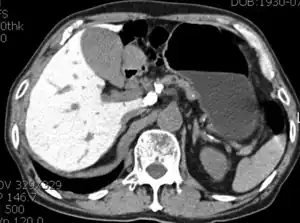

Amiodarone-induced hepatitis - CT scan showing diffuse high attenuation of the liver.

Abnormal liver enzyme results are common in patients on amiodarone. Much rarer are jaundice, hepatomegaly (liver enlargement), and hepatitis (inflammation of the liver).[31]

Low-dose amiodarone has been reported to cause pseudo-alcoholic cirrhosis.[32][33]